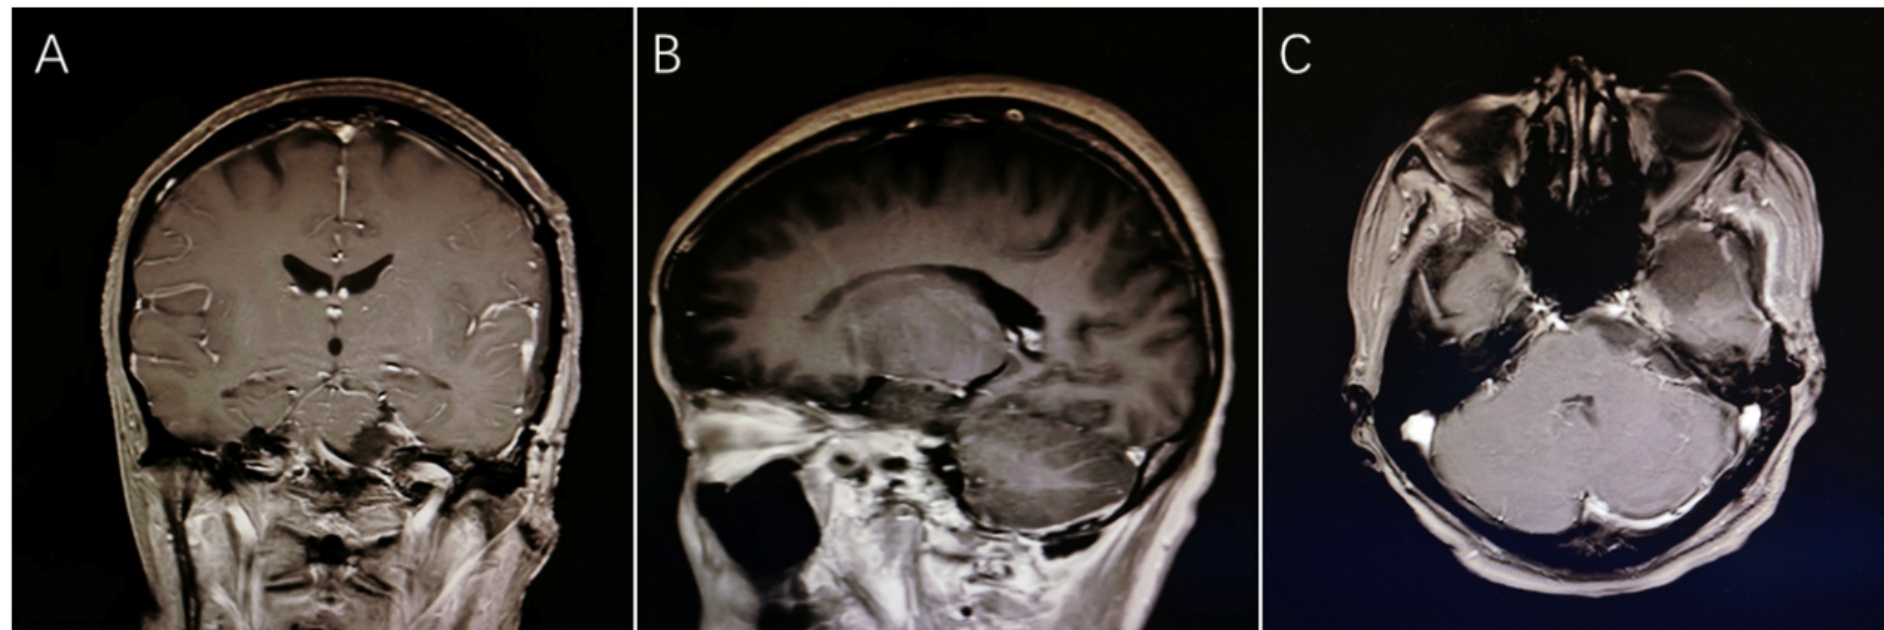

枕下乙状窦后入路是切除三叉神经肿瘤的经典术式,对起源于三叉神经根的B型(后颅窝型)肿瘤暴露最佳,同时对面听神经影响较小,从此次病例颅脑核磁平扫 + 增强影像来看,占位与海绵窦关系密切,侵袭三叉神经根部和三叉神经结,向前可达海绵窦前,单纯乙状窦后入路难以到达,故联合颞下入路处理肿瘤的海绵窦前部分[16]。术后复查颅脑核磁 + 增强(2025-06-07日)提示:未见术前肿块占位,增强扫描未见明显异常强化(图4)。术后第10天,患者的面部疼痛和麻木明显缓解。床旁听力评估与术前状态相当。后续转入肿瘤科,经PET-CT、脑脊液、骨髓细胞学检查分期为I期,予以R-MT方案免疫化疗,辅助止吐,化疗后一级预防FN治疗。出院后监测体温,每周复查血常规。术后4个月随访时的临床评估表明,患者的面部疼痛和抽搐较术前有所改善,但与术后10天的评估相比,已趋于稳定,无明显进一步改善或加重。

(A)⁓(C) 术后增强扫描显示手术区域无明显异常强化。

Figure 4. Postoperative contrast-enhanced magnetic resonance imaging (CE-MRI)

4. 术后增强磁共振成像